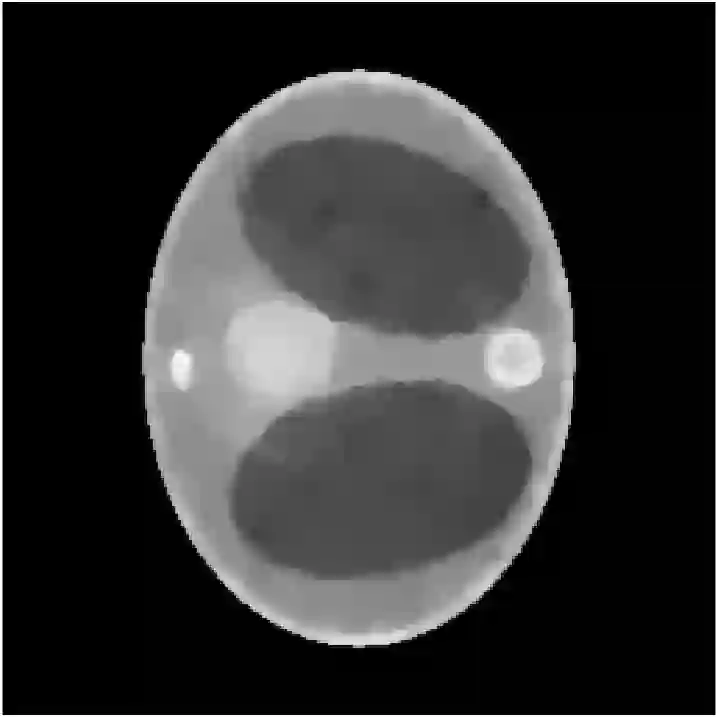

The recent development of energy-resolving scintillation crystals opens the way to new types of applications and imaging systems. In the context of computerized tomography (CT), it enables to use the energy as a dimension of information supplementing the source and detector positions. It is then crucial to relate the energy measurements to the properties of Compton scattering, the dominant interaction between photons and matter. An appropriate model of the spectral data leads to the concept of Compton scattering tomography (CST). Multiple-order scattering constitutes the major difficulty of CST. It is, in general, impossible to know how many times a photon was scattered before being measured. In the literature, this nature of the spectral data has often been eluded by considering only the first-order scattering in models of the spectral data. This consideration, however, does not represent the reality as second- and higher-order scattering are a substantial part of the spectral measurement. In this work, we propose to tackle this difficulty by an analysis of the spectral data in terms of modeling and mapping properties. Due to the complexity of the multiple order scattering, we model and study the second-order scattering and extend the results to the higher orders by conjecture. The study ends up with a general reconstruction strategy based on the variations of the spectral data which is illustrated by simulations on a joint CST-CT fan beam scanner. We further show how the method can be extended to high energetic polychromatic radiation sources.